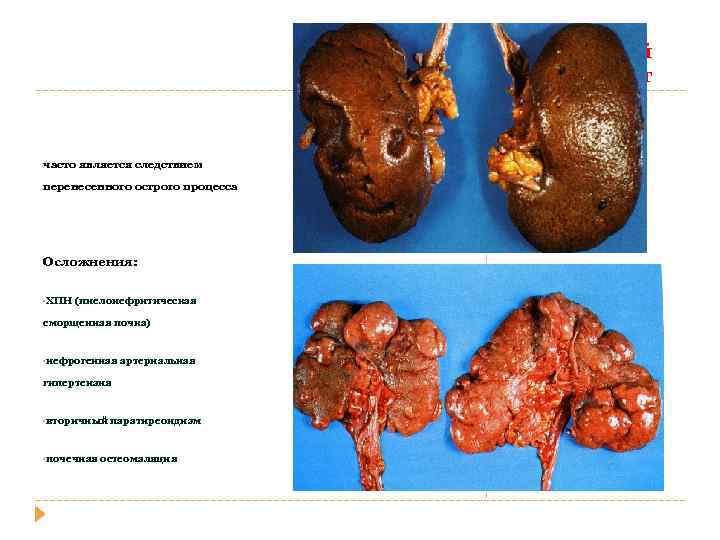

острый пиелоне фрит Гнойное воспаление с абцедированием Хронический пиелонефрит Лимфогистиоцитарная инфильтрация и склероз стромы, Перигломерулярный склероз Кистозная атрофия канальцев «тиреодизация почки» Ассиметричное сморщивание почек с грубыми рубцами

Хронический пиелонефрит часто является следствием перенесенного острого процесса Осложнения: • ХПН (пиелонефритическая сморщенная почка) • нефрогенная артериальная гипертензия • вторичный • почечная паратиреоидизм остеомаляция

Хронический пиелонефрит